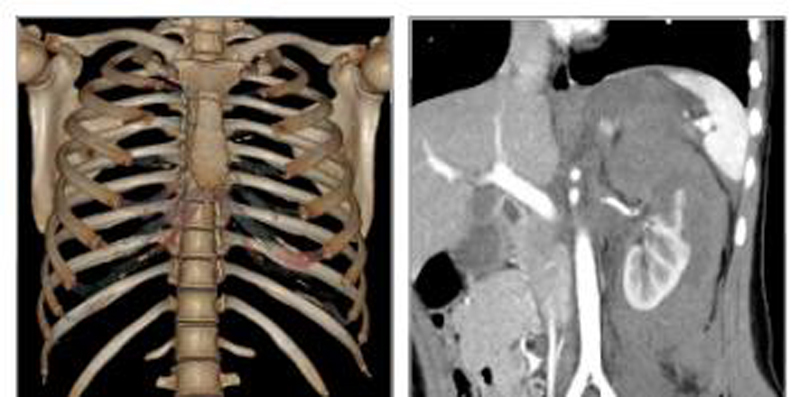

全速急诊方案

针对胸痛、脑出血、外伤、急腹症等多种急诊检查场景,天河640层CT提供全速急诊方案,检查时间最短化,图像评估直观化,为抢救生命争分夺秒。0.25秒/圈的机架转速为业内最快。